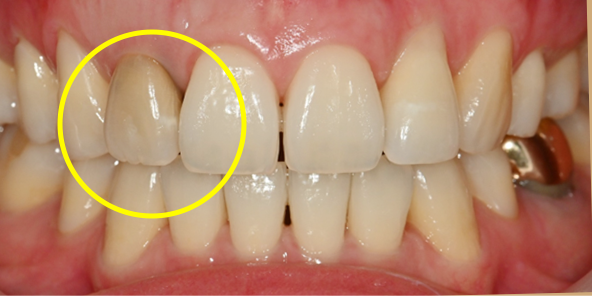

기존 임플란트

하루 완성 임플란트

임플란트를 식립하고 동시에 보철물도 완성해드립니다.

내원 당일 이루어지는 임플란트 기술력! 하루 완성 임플란트는 당일에 식립하고

임시 보철물까지 완성됩니다.